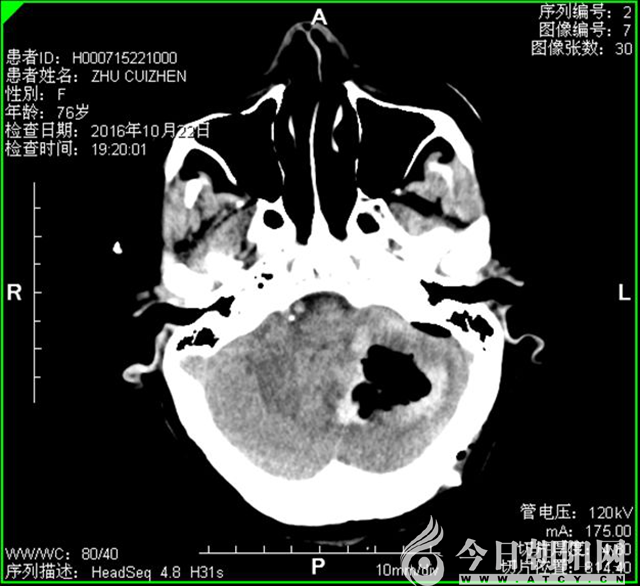

術后

神經(jīng)外二科張文主任根據(jù)患者病史及顱腦CT提示,及時向患者家屬交代病情,確定手術方案。時間就是生命,有關醫(yī)護人員迅即行動,各項術前準備工作有條不紊地進行著,患者入院不到40分鐘就被接到手術室。手術順利,術中成功清除左小腦血腫約30ml。術后1天,即拔除氣管插管,患者神清,語言流利,目前轉(zhuǎn)入普通病房康復治療中。